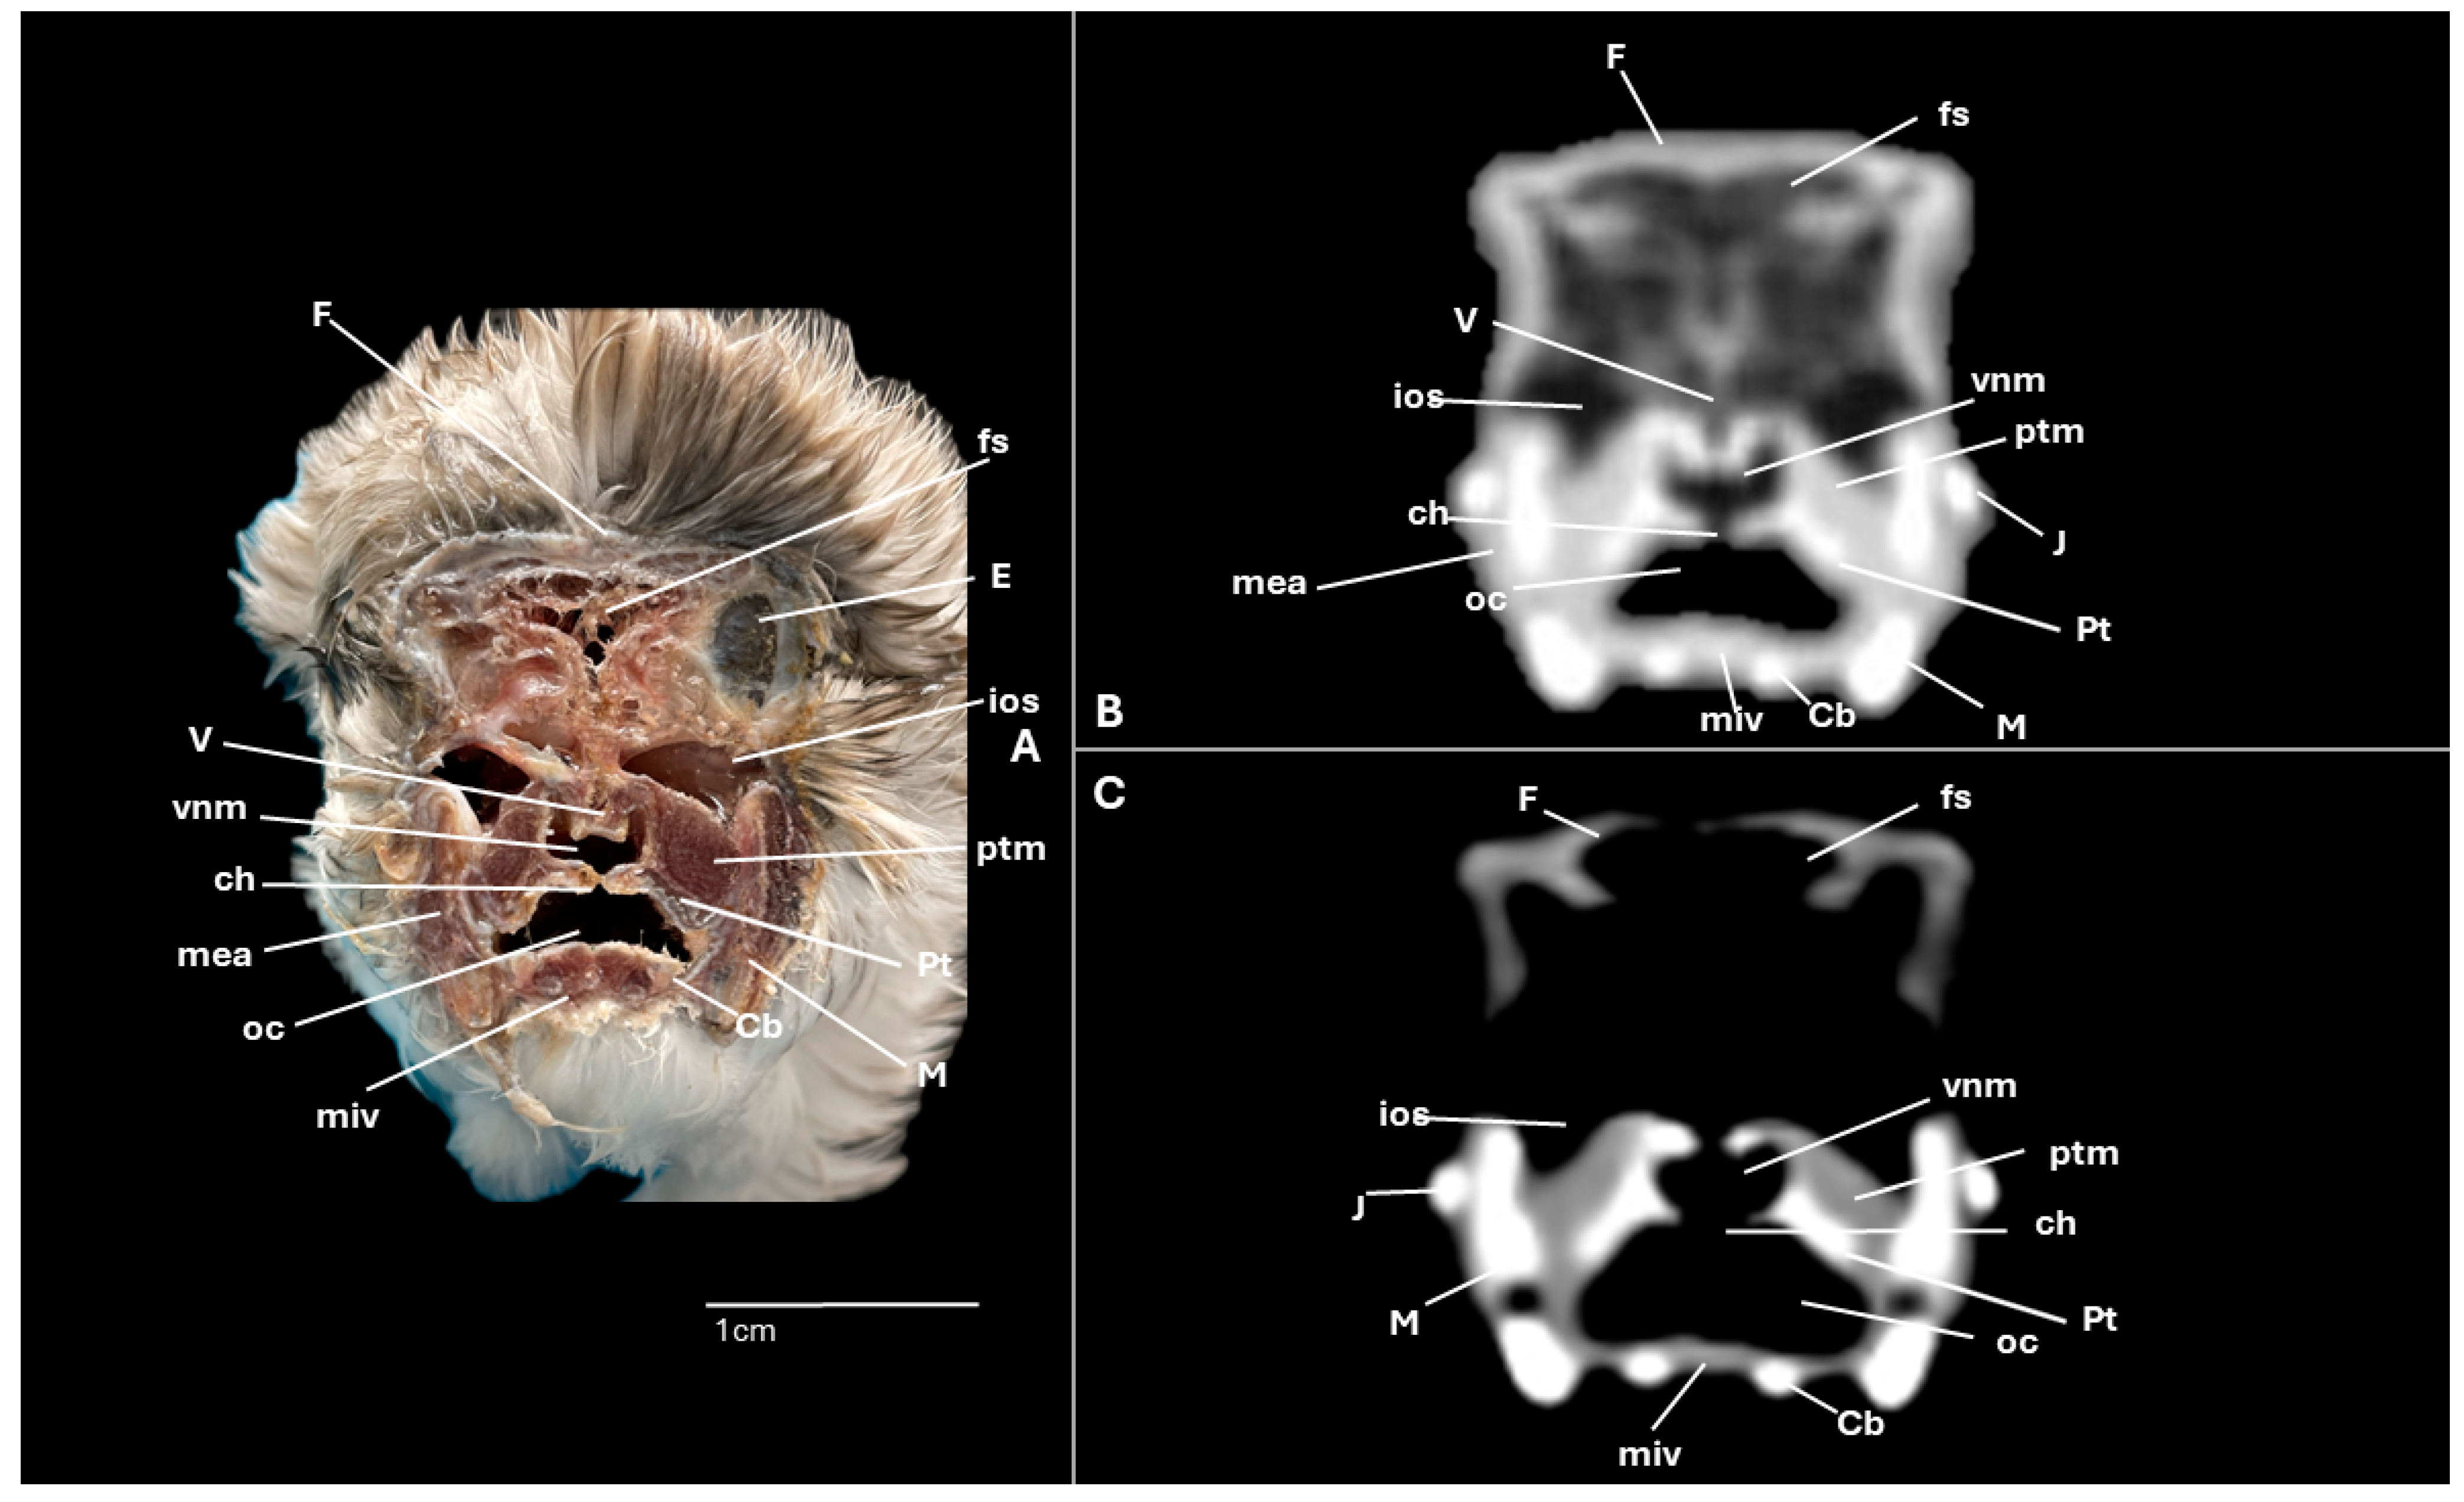

3.1. Anatomical Cross-Sections

3.2. Computed Tomography (CT)